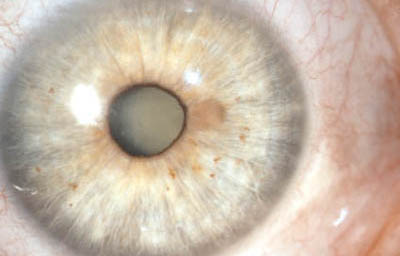

Melanoma difuso del iris

Archivo Fotográfico Dr. Francisco Barraquer.

Melanoma difuso del iris

Archivo Fotográfico Dr. Francisco Barraquer.

En la forma difusa, se aprecia una capa plana, irregular, de células pigmentadas o no, con un compromiso del iris confluente o multifocal; representa el 10% de todos los melanomas del iris. Su diagnóstico es difícil y demorado, porque frecuentemente los pacientes están siendo tratados por el cuadro de glaucoma secundario que generan. Clínicamente lo mas frecuente en su presentación es encontrar heterocromía hipercrómica unilateral y glaucoma secundario. Como dato importante, los melanomas difusos comparandolos a otros melanomas del iris, muy frecuentemente están compuestos por células epiteliodes, que tienen poca cohesión y se dispersan con facilidad en el humor acuoso, haciendo siembras en el trabéculo y estroma iridiano, y por esta razón son considerados de alto riesgo para metástasis. (33)